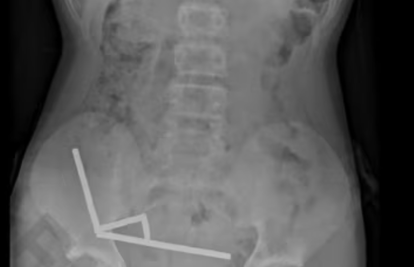

Rendgenska snimka abdomena otkrila je zastrašujući prizor - magneti su se unutar dječakovih crijeva grupirali u četiri kompaktne linije...

Rendgenska snimka abdomena otkrila je zastrašujući prizor – magneti su se unutar dječakovih crijeva grupirali u četiri kompaktne linije.

"Činilo se da se nalaze u odvojenim dijelovima crijeva koji su se slijepili zbog snažne magnetske sile", pojasnili su liječnici. Taj pritisak uzrokovao je nekrozu, odnosno odumiranje tkiva, na četiri mjesta u njegovom tankom i slijepom crijevu.